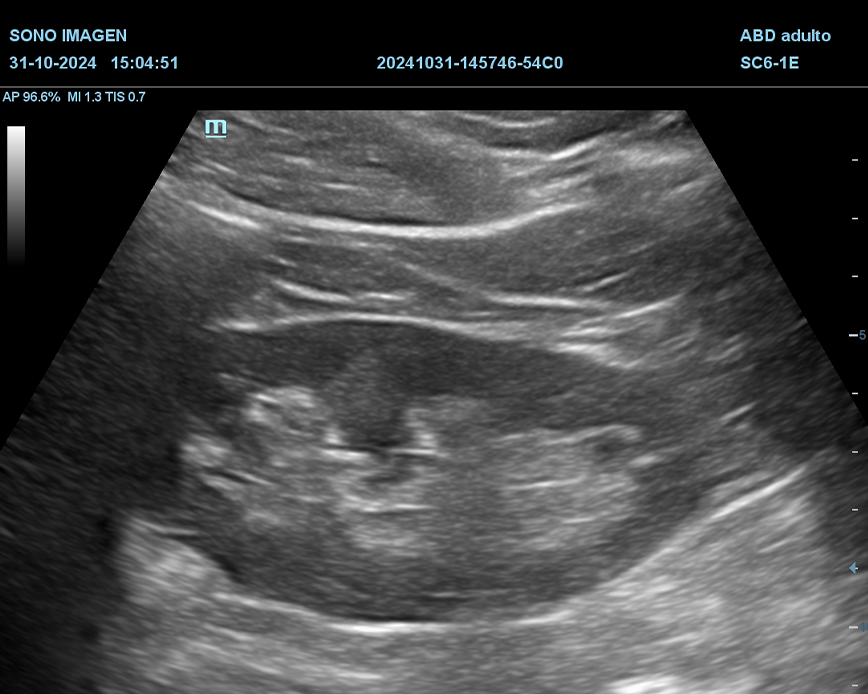

Ecografía Prostática

- hiperplasia prostática benigna(HPB)

- cáncer de próstata

- prostatitis

- dificultad para orinar o retención urinaria

- hematuria

- alteraciones en la fertilidad masculina

- control postquirúrgico o postratamiento

- anomalías detectadas en estudios previos

- quistes prostáticos